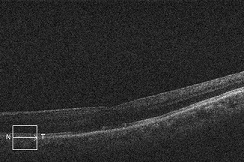

?正常な網膜です。中心部の赤い部分の網膜には、物を見るための視細胞が沢山集まっています。その周りの青にも、視細胞がありますが、赤に比べると数が少なくなります。緑はさらに見え方が落ちる部位です。